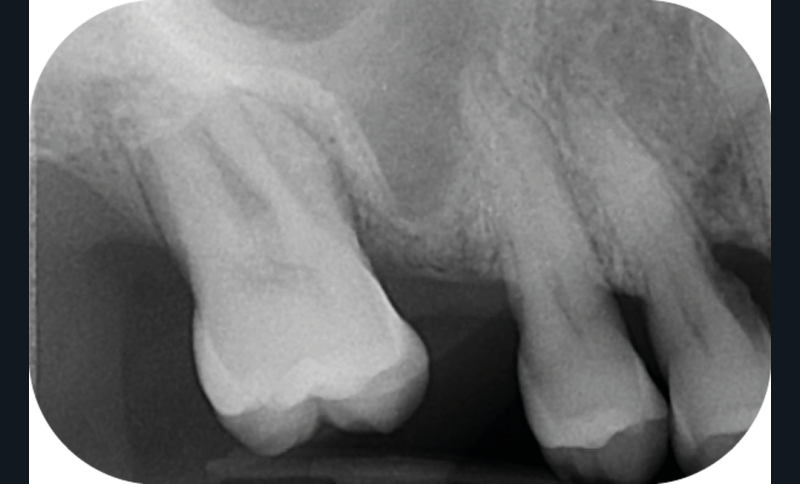

La perte d’une ou plusieurs dents entraîne la perte des points de contact, responsables de la stabilité et de la continuité de l’arcade. Par conséquent, une avulsion a pour première conséquence la migration ou la version d’une ou plusieurs dents distales (fig. 1 et 2). Cela est vrai en antérieur comme en postérieur.

L’âge de survenue de l’extraction semble avoir une importance sur l’apparition des migrations et des versions : si l’édentement intervient après 26 ans, les conséquences sont moins fréquentes [9].